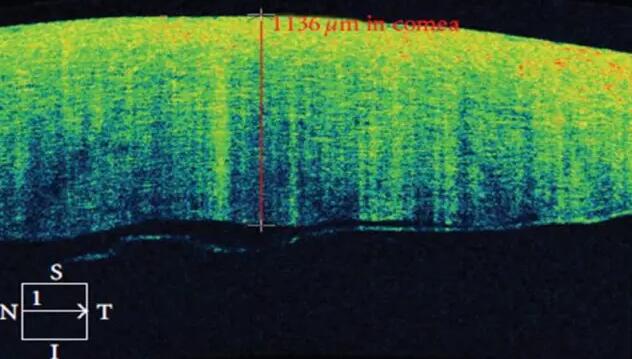

1、角膜分层观察 OCT 轴向分辨率高达5μm,远高于UBM(20--60μm),可识别出泪膜、上皮层、前弹力层、基质层、后弹力层/内皮层

2、角膜厚度评估,角膜水肿、瘢痕、混浊、溃疡、异物、炎症、胬肉等断层观察